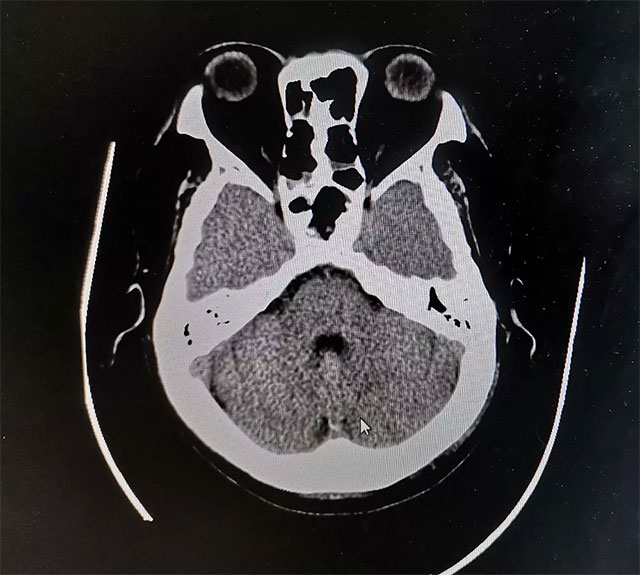

潘仁龍主任指出,CT在垂體卒中急性期平掃時(shí)即可見(jiàn)瘤內(nèi)的高密度影出血灶,很容易辨別,但當(dāng)進(jìn)入亞急性期后則呈等密度,難于鑒別。因此,在高度懷疑垂體卒中的病例中應(yīng)首選MRI掃描。此外,MRI 還能提供較 CT 更為清晰的三維空間解剖結(jié)構(gòu),它對(duì)腫瘤以及瘤體與周邊正常組織的關(guān)系都可起到良好的顯示作用。因此MRI是垂體瘤卒中的首選影像學(xué)檢查手段,而在急性期,尤其是超急性期則首選CT。

▲ 術(shù)后影像顯示腫瘤被切除